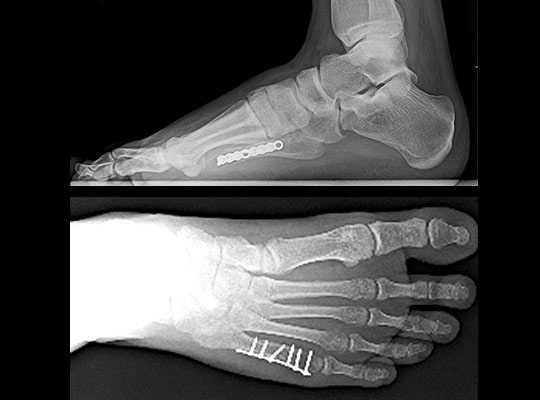

Рентгенограмм в 2-х проекциях обычно достаточно, чтобы диагностировать перелом. Но при стресс-переломах без смещения, иногда, их невозможно определить даже очень опытному врачу.

В таких случаях назначаются контрольные рентгенограммы через 10-14 дней, когда происходит резорбция костной ткани в месте перелома. Так же стресс переломы трудно увидеть на рентгеновских снимках, пока они не начали срастаться и не начала образовываться костная мозоль. Как раз её очень хорошо видно на рентгенограммах. Компьютерная томография или МРТ могут быть необходимы для исключения стресс перелома и других патологий стопы.

Чрескожная фиксация спицами

Была популярна на протяжении многих лет и продолжает оставаться одним из самых популярных методов в международном масштабе.

Сначала врач закрыто устраняет смещение отломков, затем через отломки в определенных (учитывая характер перелома) направлениях просверливаются спицы.

Плюсы: малая травматичность, быстрота, легкость, дешевизна, отсутствие разреза и как следствие послеоперационного рубца.

Минусы: концы спиц остаются над кожей, для того чтобы спицу можно было удалить после срастания перелома; риск инфицирования раны и проникновение инфекции в область перелома; длительное ношение гипсовой повязки 1 месяц; неудобства в повседневной жизни.

Открытая репозиция перелома

Открытая репозиция при переломе плюсневой кости стопы, накостный остеосинтез пластиной и винтами. Операция включает в себя хирургический разрез, доступ к сломанной плюсневой кости аккуратно отводя сухожилия, сосуды и нервы, мобилизацию костных отломков, устранение смещения и фиксация в правильном положении.

Гипсовая иммобилизация не проводится, так как металлоконструкция, фиксирует отломки.

Разрешается ходьба с опорой на пяточную область в течение месяца.